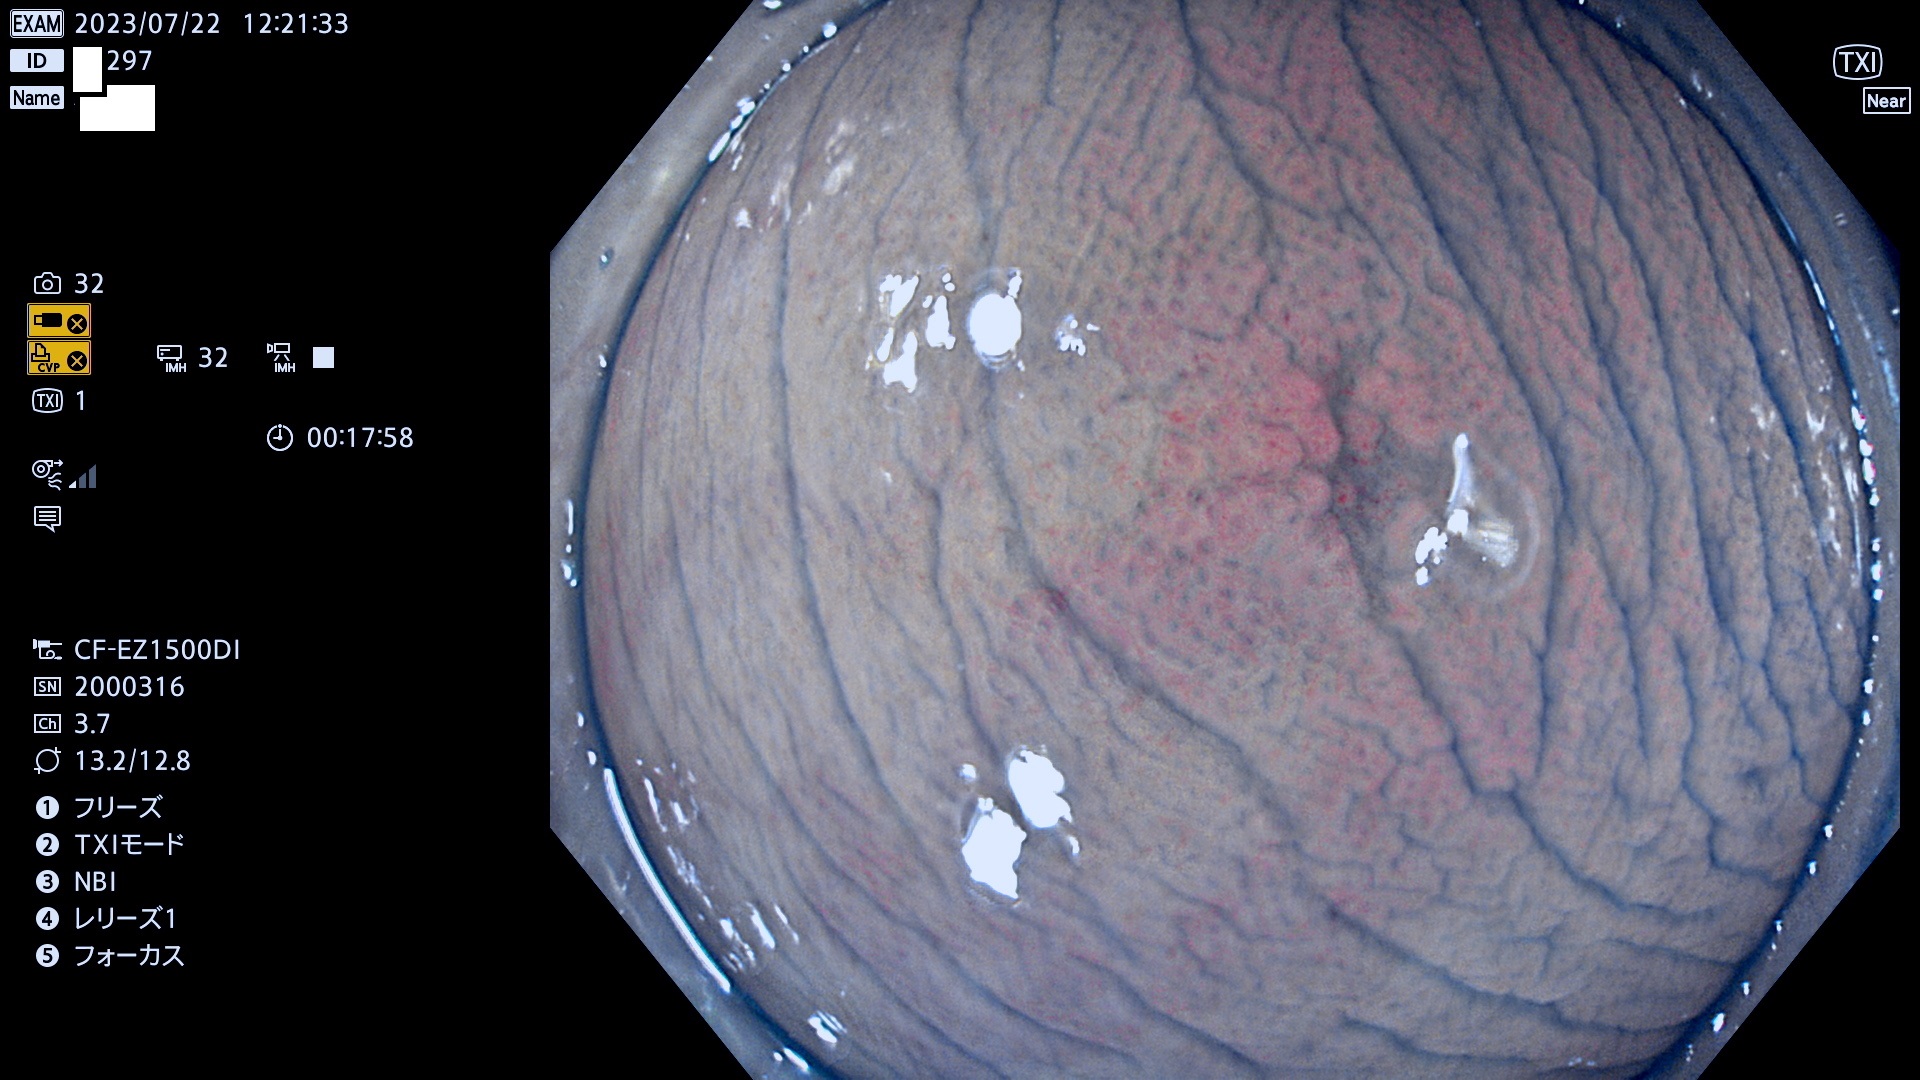

「表面型腺腫(Flat Adenoma)の中で、完全に平坦な物をUb、陥凹している物をUcと呼びます。平坦隆起型(Ua)よりも、発見が難しく危険な病変です。このタイプは「内視鏡後・大腸癌の重要犯人」であり、この発見率は「腺腫発見率」よりも、重要な意味があります。

毎週の検査(木・金・土・日)に発見されたUb、Uc型・腺腫を、その週の日曜の夜にUPし1週間、提示します。

抽出の対象期間 2023年7月20日(木)〜7月23(日)の4日間(48件の検査)12件